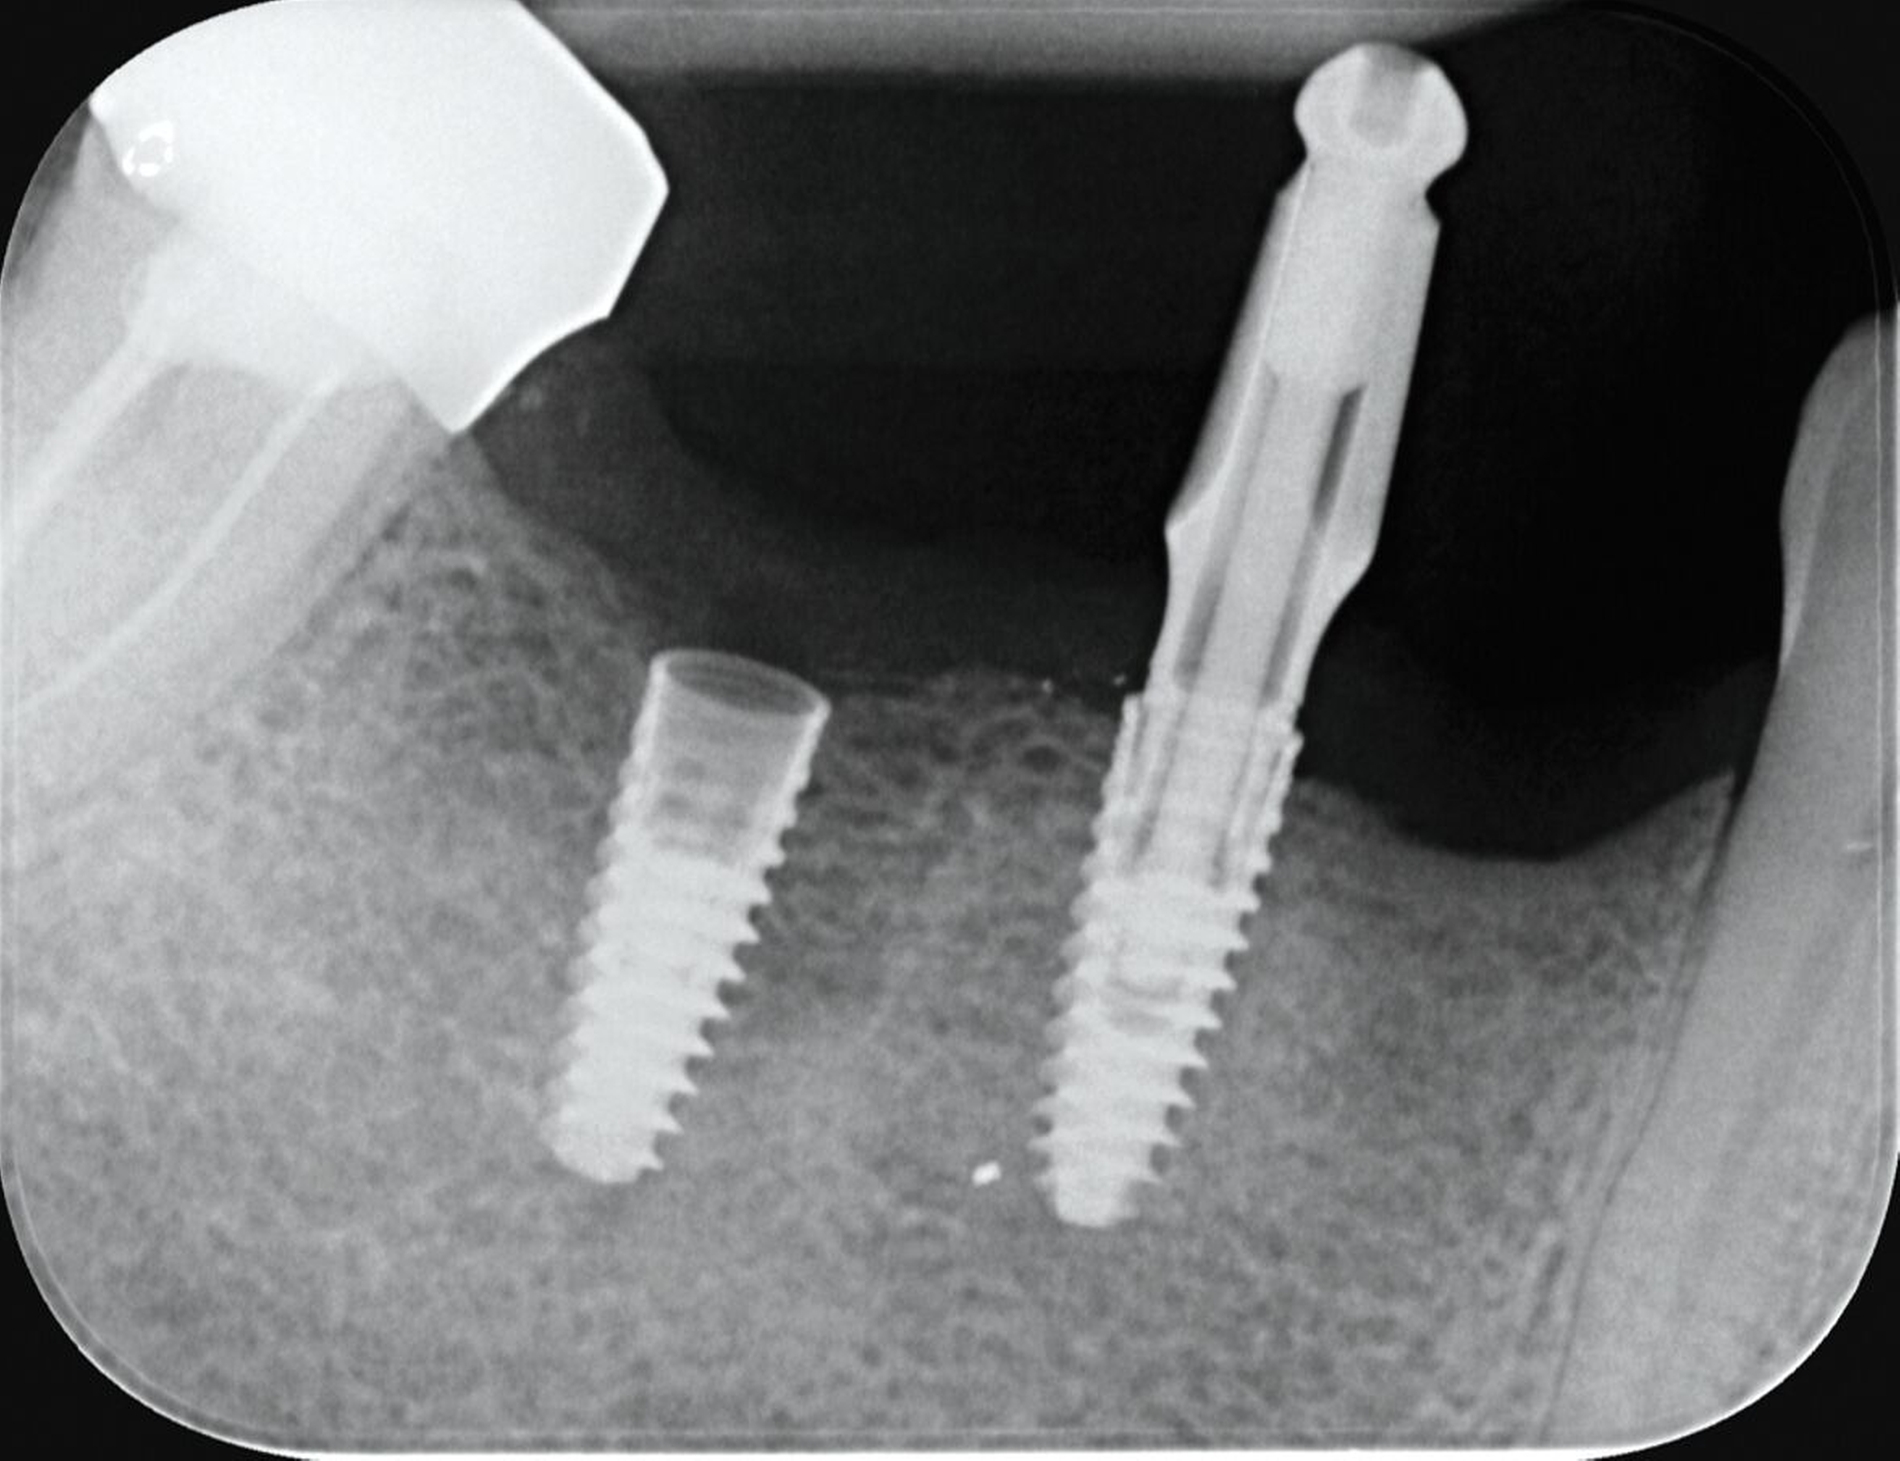

In diesem Fall kam es durch die Verwendung nicht originaler Komponenten zur Befestigung eines Langzeitprovisoriums zu einer Abnutzung des Konnektors im Schraubenkopf. Beim Versuch, das Provisorium im Rahmen der definitiven Abformung zu entfernen, ließ sich das Abutment nicht mehr lösen (Abbildung 5). Nach Abnahme des Kunststoffteils wurde zunächst versucht, eine Rille zur Aufnahme eines schlitzförmigen Schraubendrehers mithilfe eines kleinen Rundbohrers (zum Beispiel EKR-Bohrer) zu fräsen (Abbildung 5). Aufgrund der verbliebenen Grate war jedoch keine effektive Kraftübertragung möglich. Schließlich erfolgte eine zirkuläre Entgratung des Schraubenkopfs mit einem diamantierten Ultraschallinstrument gegen den Uhrzeigersinn. In der Folge ließ sich die Schraube durch kontinuierliche Linksdrehung erfolgreich aus dem Implantat entfernen (Abbildung 6).

Hier kam es zum Verlust einer verschraubten Brückenkonstruktion auf einem neueren Implantatsystem (Abbildung 7). Vermutlich lag eine Kombination aus Überbelastung, unzureichender Passung, inadäquater Vorspannung oder der Verwendung nicht definitiver (zum Beispiel laborseitiger) Schrauben vor, die schließlich zum Bruch der Abutmentschrauben führte.

Glücklicherweise konnten die Schraubenfragmente im Implantat einfach entfernt werden. Mithilfe einer Wurzelkanaleingangssonde wurden sie unter dem Operationsmikroskop vorsichtig gegen den Uhrzeigersinn gedreht und ohne weiteren Schaden aus dem Implantatinneren gelöst.